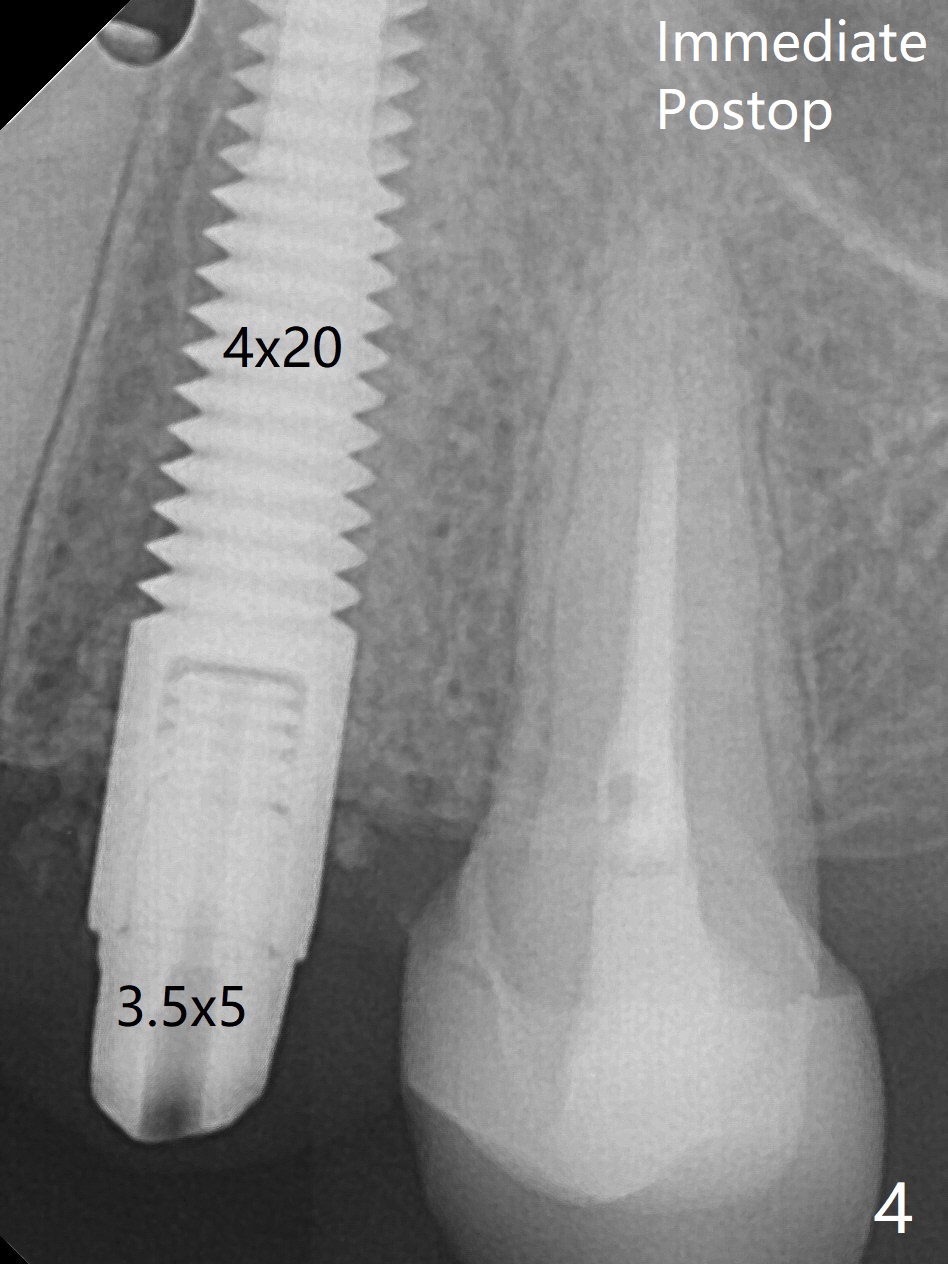

一个月前12号牙仅有隐裂(与术前即刻(图一)对比),当时CT显示轻度颊侧根尖缺损(图二:>)。拔牙后颊侧根尖没有骨板,所以钻洞偏腭侧(图三);完成最后钻头(3毫米)后,后者保持原位,先在颊侧根尖植骨,然后取出钻头,植入植体(图四),放置基台后,在后两者周围再置入骨粉,最后制作临时牙冠固定骨粉。由于骨质密度低(图二;术中钻洞容易),选择20毫米植体,扭力50Ncm。